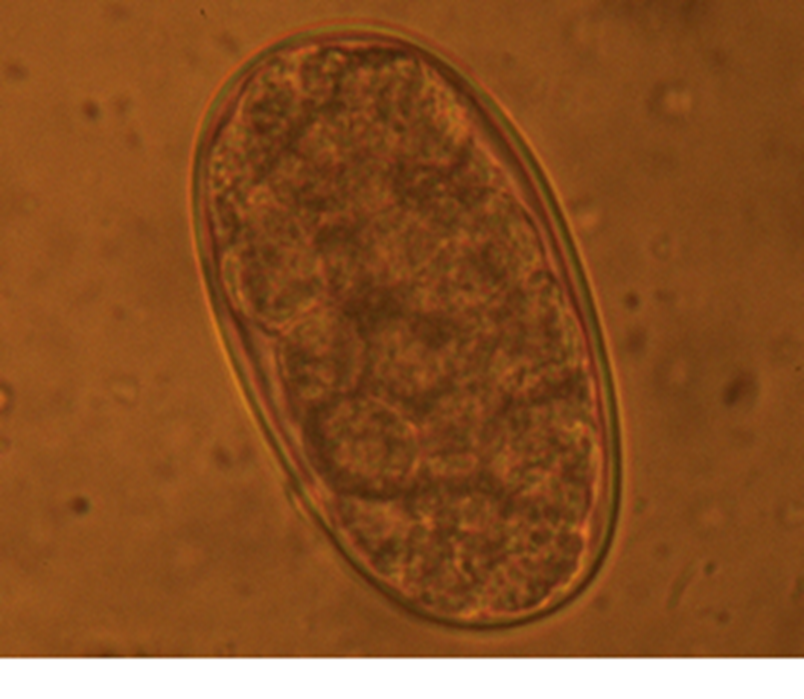

Both of these worms have a direct life cycle in that no other animals are involved in the life cycle. The eggs produced are relatively fragile and will die if dehydrated. (Fig 2.)

Fig 2: Strongyle egg found in sow faeces

Clinically, these two worms have traditionally been linked to the "thin sow syndrome" and any animal suffering poor body condition should be suspected of being infected and treated accordingly. Moreover, immunity to these two worms is poor and as such repeated exposure and build-up of eggs and larvae within the environment will simply progressively increase the burden on the pig, irrespective of age.